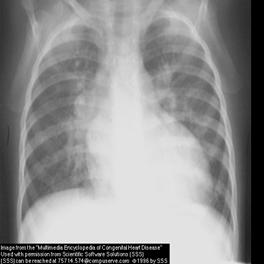

4.RX

:

Cardiomegalie implicand in special AS,VS,rareori VD.Circulatie pulmonara incarcata.Gradul cardiomegaliei si cresterea circulatiei pulmonare sunt direct relationate cu magnitudinea suntului.

In BPVO AP si ramurile sunt f.dilatate,dar periferia pulmonara este ischemica.